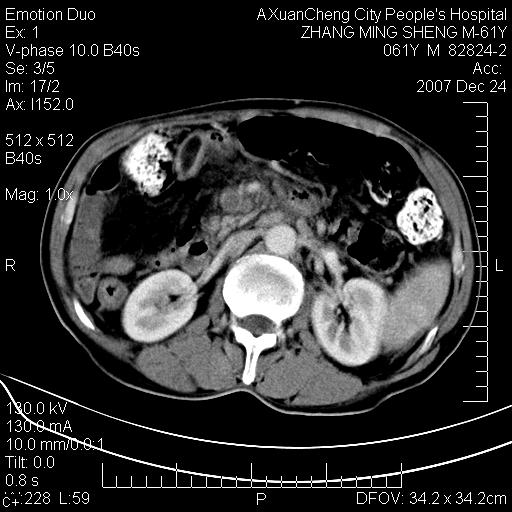

标题: CT11031:M61Y,胰腺占位 [打印本页]

标题: CT11031:M61Y,胰腺占位

大家侃侃门静脉和胆管系统怎么回事,肝内转移?

胰腺癌肝转移

肝硬化,门脉高压,脾肿大;弥漫性肝癌,肝内、门脉、腹膜后淋巴结转移,肝内外胆管扩张,胰头区占位,建议mr检查

胰腺癌伴肝内转移;门脉、肠系膜上v癌栓形成。

考虑为:胰腺癌伴肝脏转移、腹膜后淋巴结转移,门静脉及肠系膜上静脉瘤栓形成。

胰体尾癌伴肝内转移,门静脉及肠系膜上静脉瘤栓形成.

肝硬化,脾大. 胰腺癌伴肝内转移;门脉、肠系膜上v癌栓形成。